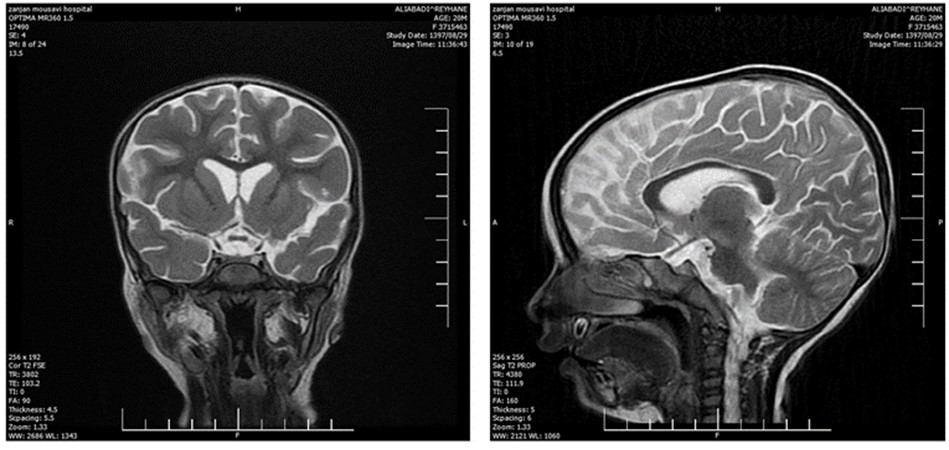

The laboratory evaluations indicated mild anemia; her CSF, ESR, CRP, CXR, and echocardiography were within the normal range. Brain CT investigation and MRI analysis of the brain indicated brain edema and hypersignality, respectively (Figure 1 - 2). Furthermore, EEG showed diffused low-voltage slow waves due to encephalopathy.

Figure 1. The CT of brain in current patient

Figure 2. The MRI analysis of the brain